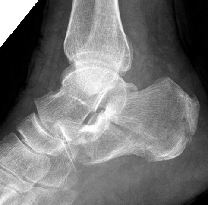

患者术前影像显示根骨粉碎性骨折

近日,市民程某因不小心摔倒,感觉足部疼痛难忍,于是来我院骨科中心就医,经过仔细检查诊断为粉碎性跟骨骨折;对于粉碎性跟骨骨折,需要尽快采取手术复位固定,否则,极易造成畸形愈合,影响足部正常功能。